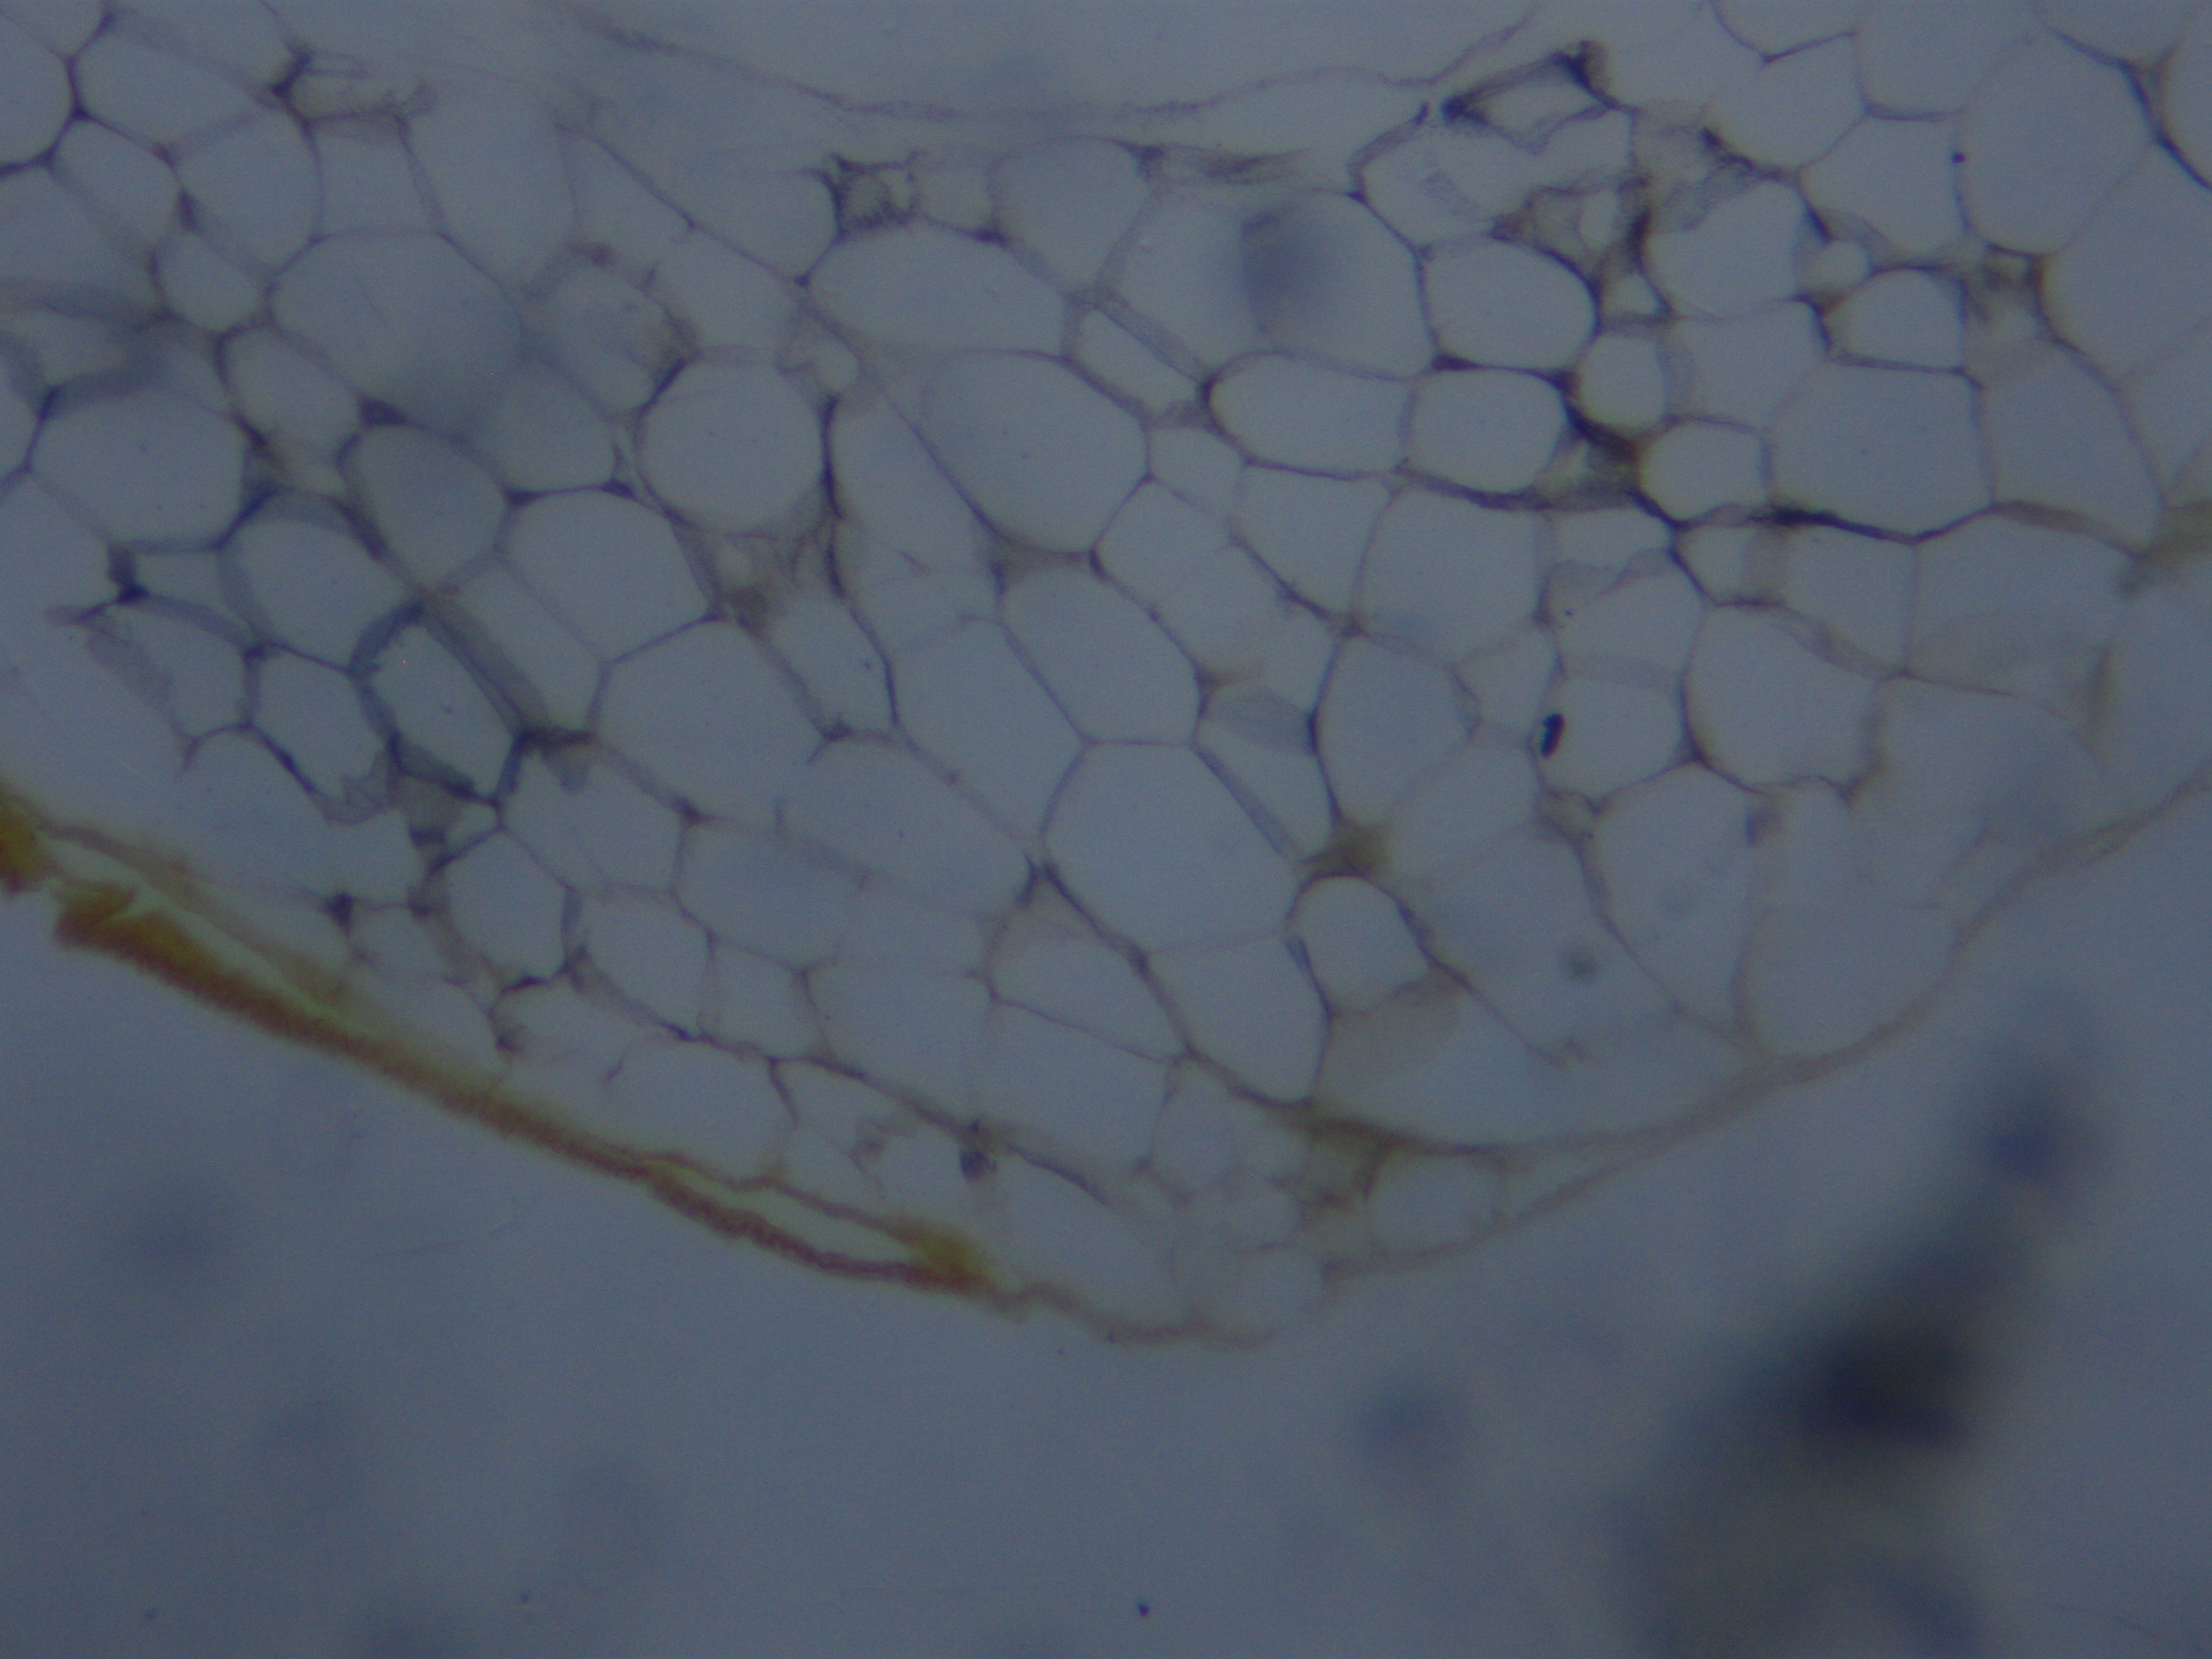

Adipose connective tissue